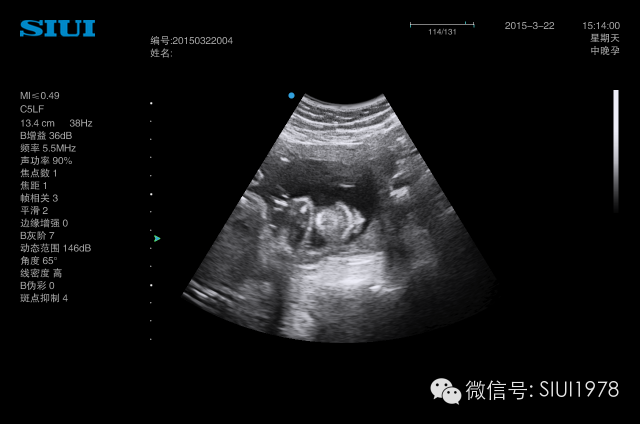

(三)正中矢状切面

1.扫查方法:胎儿仰卧位,探头置于胎儿面部正前方,声束平面通过胎儿鼻尖和额部作正矢状切面扫查,即可获此切面。

2.判断标准:下颌骨仅为圆点状高回声,鼻尖显示的同时只显示鼻柱,而不能显示鼻孔,同时显示额部而非眼眶回声。

3.主要观察的解剖结构及内容:前额、 鼻根、 鼻尖、 鼻柱、 上唇、 下唇、下颌及其深部的骨性结构如额骨、 鼻骨、上颌骨牙槽突、 下颌骨牙槽突,还可观察到口腔及舌,下巴则表现为有一定曲度的“S” 形。声束平面略向左或右平行移动,可显示出鼻孔、 眼球等结构。

4.临床意义:该切面是观察胎儿面部轮廓的良好切面,某些特征在诊断与鉴别诊断颜面部异常时有非常重要的意义,尤其是有面部中线异常的畸形,该切面诊断意义较大,如前额后缩(小头畸形)、前额前凸(颅内肿瘤及额部脑膨出)、无鼻或鼻发育不良、喙鼻、鼻骨发育不良或缺失、 、 双侧唇腭裂所致上颌骨前突、口腔畸胎瘤、舌血管瘤、小下颌、无下颌并耳畸形等。